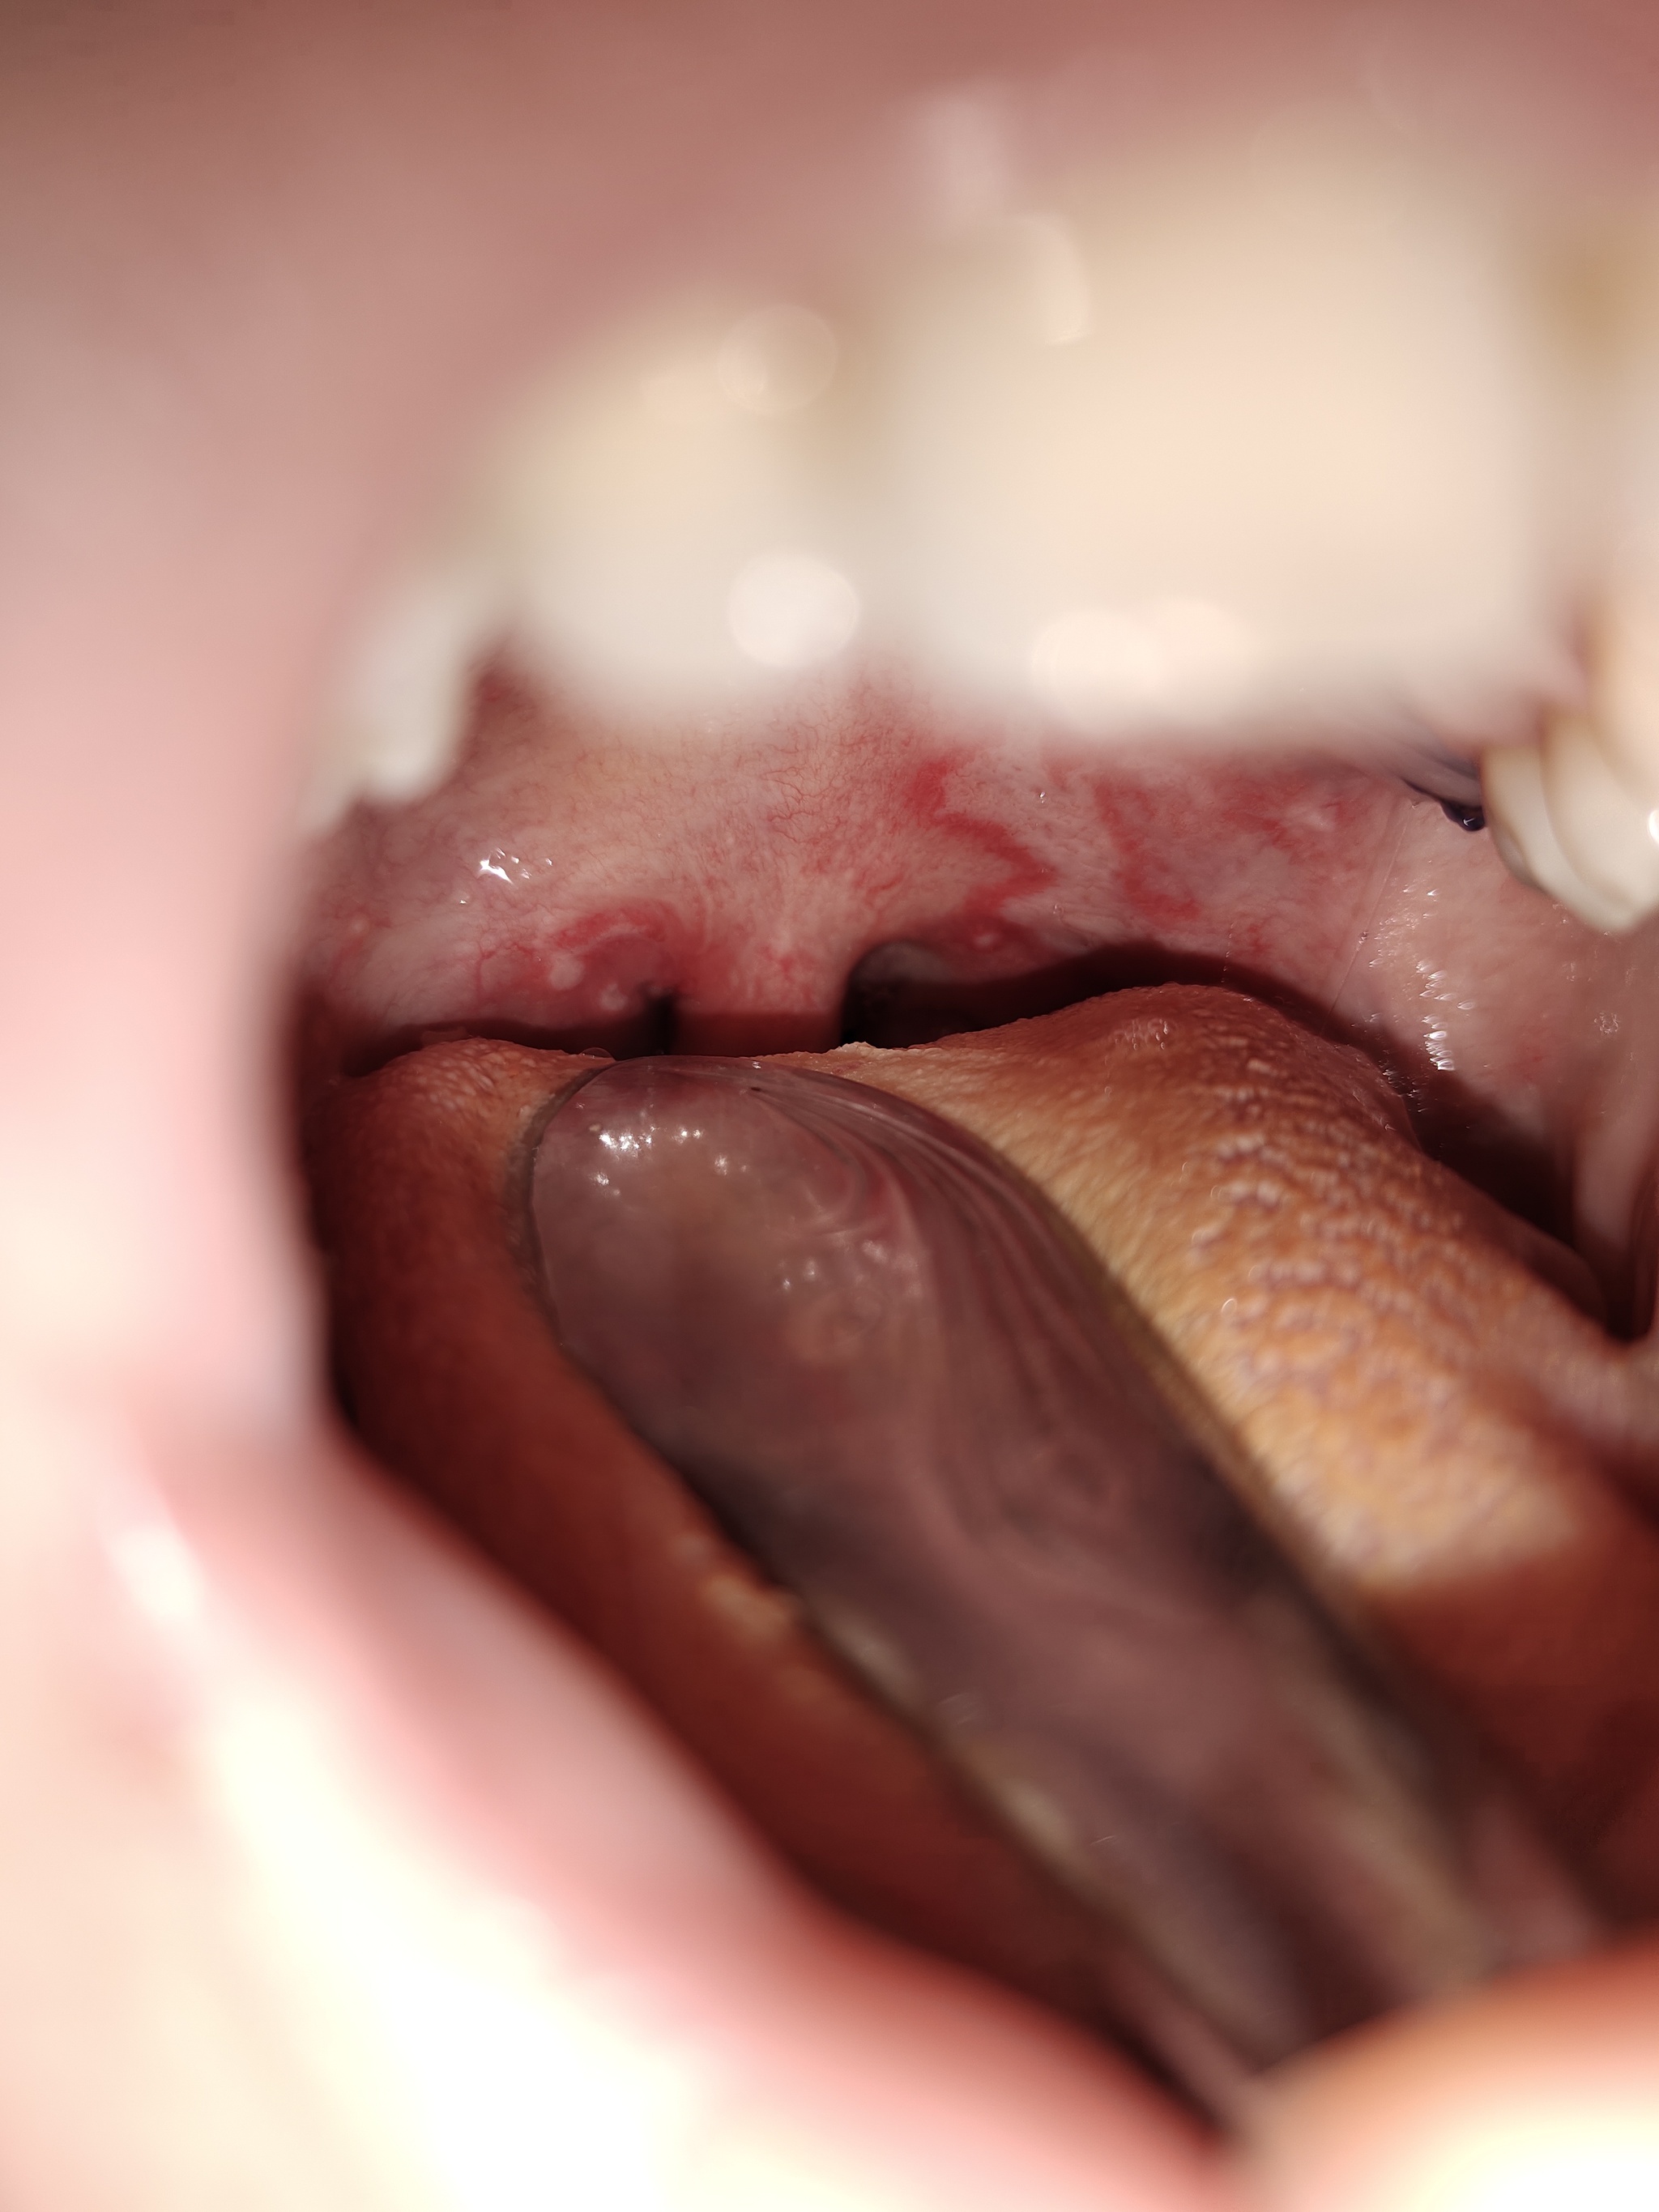

Делюсь этим с врачом на осмотре. Она подтверждает, что на горле есть язвы, скорее всего острая реакция на интубацию. Полоскать, терпеть, ждать. Должно пройти завтра - послезавтра.

Лор при осмотре определяет у меня герпетический стоматит. Объясняет, что это вообще не по ее специальности, это должны были выявить стоматологи. Выписала мне ещё один список лекарств.

- Ну да, поражение у вас очень сильное и обширное, наверно очень болезненное...